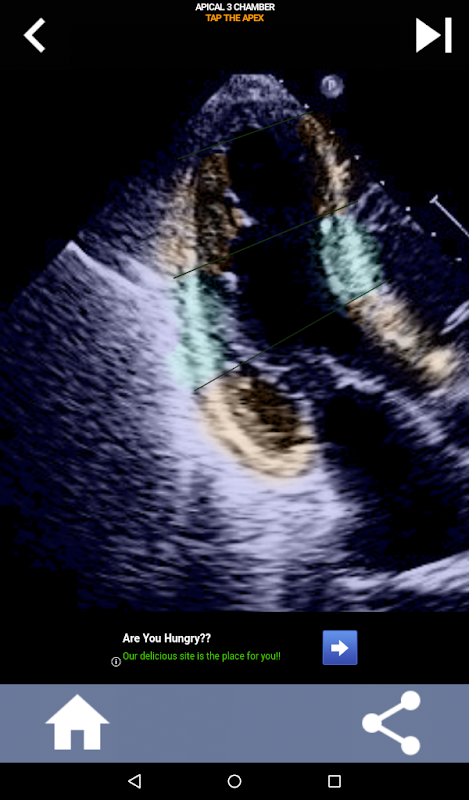

Enfoque visual basado en cuestionarios para aprender los segmentos cardíacos de la AHA: ecocardiografía

Comprender los segmentos cardíacos de la AHA (Asociación Estadounidense del Corazón) es de suma importancia para que un ecografista cardíaco se comunique de manera efectiva con el cardiólogo que escribe el informe. Al conocer las regiones anatómicas específicas y sus segmentos correspondientes, el ecografista puede describir y comunicar con precisión cualquier anomalía o hallazgo, asegurando una comunicación clara y concisa entre ambos profesionales.

Esta comprensión se vuelve particularmente crucial cuando el cardiólogo busca determinar la ubicación precisa de un problema o cuando el médico de guardia identifica un problema dentro de una región específica, lo que hace que el ecografista muestre con precisión el segmento correspondiente, como la pared inferior media. Por lo tanto, poseer una comprensión integral de los segmentos cardíacos de la AHA es un conjunto de habilidades esencial.

Esta aplicación pondrá a prueba su conocimiento utilizando imágenes de eco reales, que a menudo encuentro que es el mejor método de enseñanza.